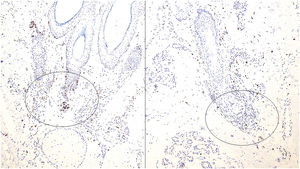

Histopathologically, scarring alopecia is primarily characterized by fibrosis, often perinfundibular, along with the destruction of elastic fibers, which may require special histochemical techniques for detection (Fig. 1A and B). Recently, Botega et al. described early histological markers that differentiate scarring from non-scarring alopecia before elastic fiber destruction occurs.2 Non-scarring alopecia typically exhibits a higher follicular density, with an increased number of non-terminal and miniaturized follicles2 (Fig. 1C). In contrast, scarring alopecia is often associated with dermal inflammatory infiltrates concentrated around the permanent portion of the follicle, frequently in a lichenoid pattern.2 Additional features include syringoma-like ductal proliferation, arrector pili muscle pseudohyperplasia, and reduced sebaceous gland density.2 Inflammatory infiltrates are particularly prominent in scarring alopecia associated with chronic discoid lupus erythematosus (CDLE). While CDLE is the primary scarring sign of alopecia in lupus, most alopecic presentations in lupus are non-scarring.

(A) Presence of concentric perinfundibular fibrosis, easily identifiable with haematoxylin and eosin staining, in a case of scarring alopecia. (B) Histochemical staining using the orcein technique, demonstrating the destruction of elastic fibres in the perinfundibular areas of a case of scarring alopecia. (C) Example of androgenetic alopecia (non-scarring), with marked follicular miniaturisation. (D) Biopsy of an alopecic patch in a patient with lupus erythematosus. Presence of a superficial and deep perivascular inflammatory infiltrate, along with perianexal involvement, dermoepidermal junction blurring, and epidermal atrophy. (E) Detail of the same case shown in figure LUPUS showing vacuolar degeneration of the basal layer of the epidermis with some apoptotic keratinocytes.